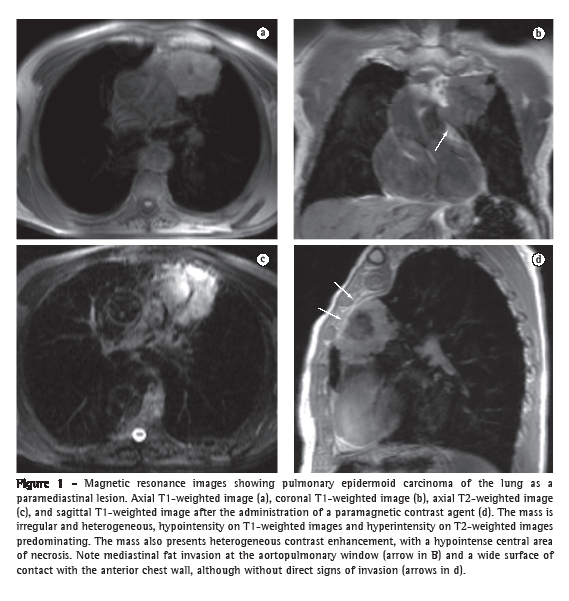

In general, bronchogenic carcinoma appears on MRI as a solid, irregular lesion, ranging from hypointense to isointense on T1-weighted images and hyperintense on T2-weighted images, with intense enhancement after the administration of contrast material, being heterogeneous in larger lesions due to areas of central necrosis. Even in lesions outside the superior sulcus, MRI can better identify direct invasion of adjacent structures (Figure 1), including the mediastinum (aortopulmonary window and remaining spaces), trachea, bronchi, chest wall, diaphragm (costophrenic angle tumor and cardiophrenic angle tumor), heart (pericardium or myocardium), and large blood vessels (aorta and pulmonary arteries). The sensitivity of MRI in differentiating between T3 and T4 tumors is similar to that of CT. However, MRI is more accurate in identifying mediastinal and hilar invasion. The use of dynamic cine MRI can increase MRI specificity in detecting invasion of the chest wall and pericardium. New MRI techniques have increased the sensitivity of the test in detecting mediastinal lymph nodes that are suspected of being metastatic. A short inversion time (TI) inversion recovery sequence (a T2-weighted technique with fat suppression by inversion and recovery) allows the differentiation between metastatic and non-metastatic lymph nodes in patients with non-small cell tumors, metastatic lymph nodes being more intense.(12-15)

In the characterization of central lung cancer with obstructive pneumonia or atelectasis, MRI is useful and differentiates a tumor mass from secondary changes, which present increased signal intensity on T2-weighted images and a more homogeneous appearance (due to the accumulation of secretions and fluid), as well as an enhancement pattern that is different from that of the neoplastic lesion.(34) In invasive pulmonary aspergillosis, MRI is more specific than CT in characterizing consolidations associated with hemorrhagic infarction secondary to vascular invasion (Figure 4).